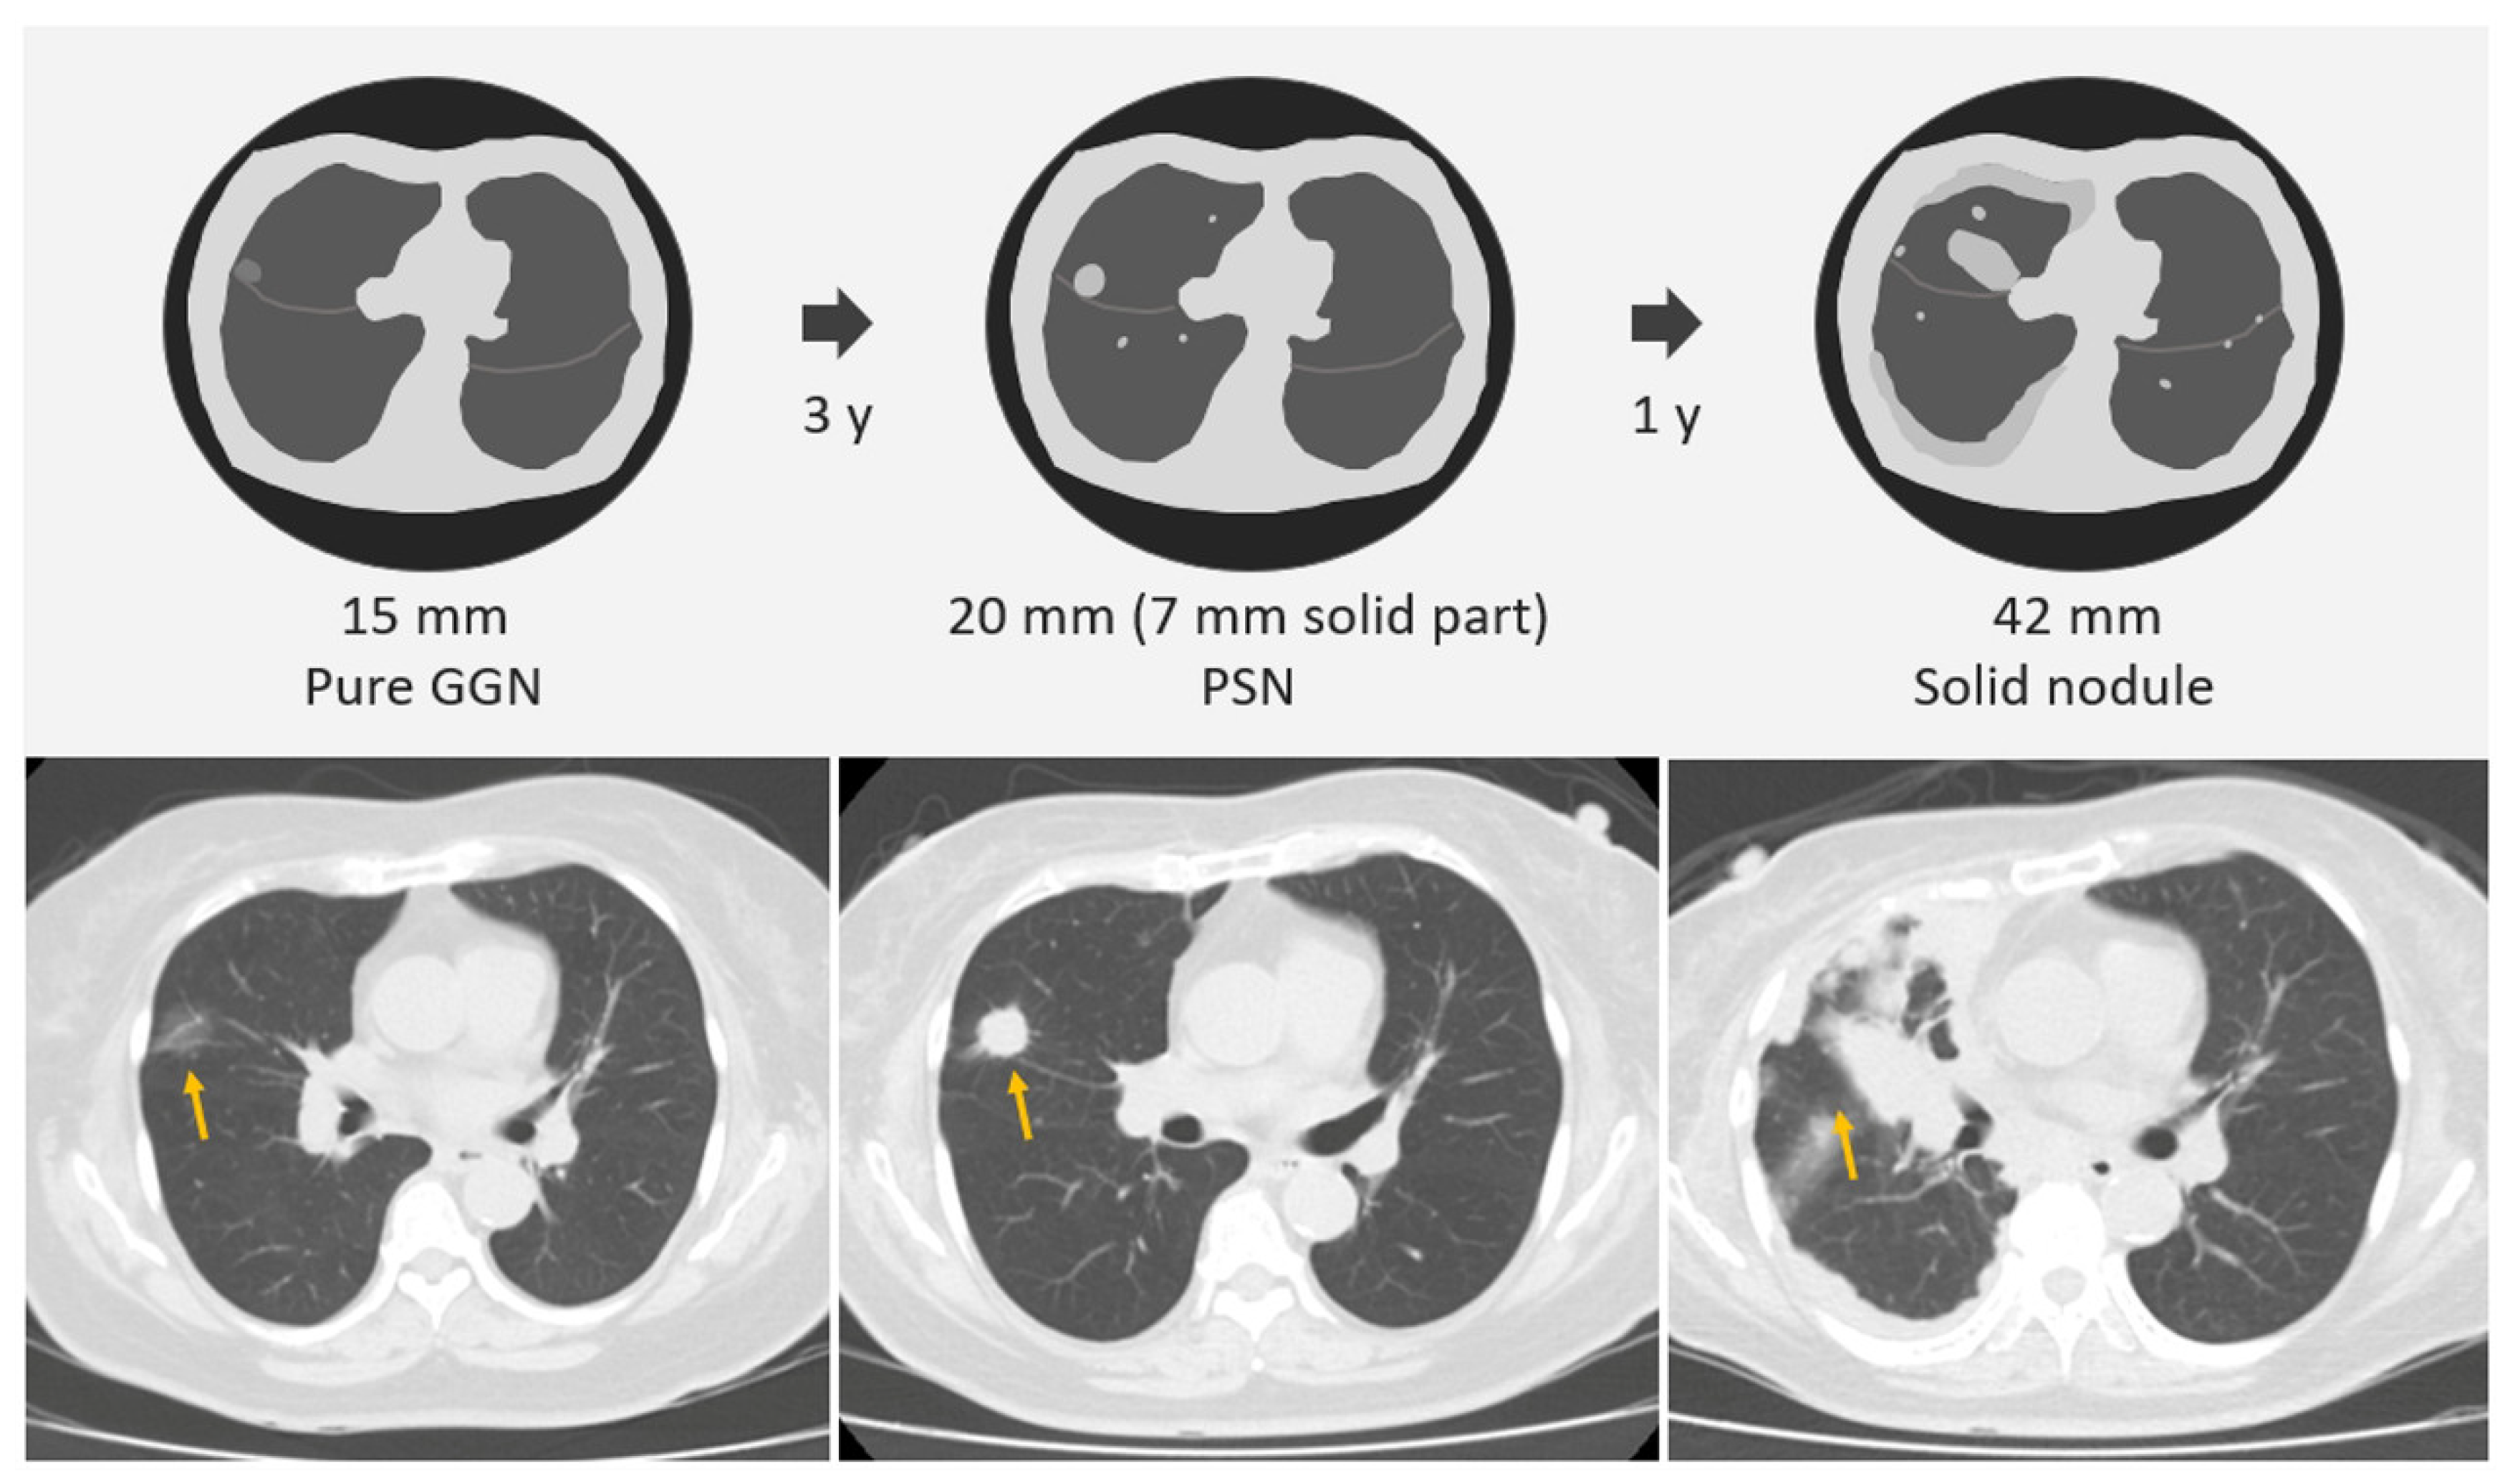

2.3. SSNs Interval Growth with Clinical Stage Shift

- Tang, E.-K.; Chen, C.-S.; Wu, C.C.; Wu, M.-T.; Yang, T.-L.; Liang, H.-L.; Hsu, H.-T.; Wu, F.-Z. Natural History of Persistent Pulmonary Subsolid Nodules: Long-Term Observation of Different Interval Growth. Heart Lung Circ. 2019, 28, 1747–1754. [Google Scholar] [CrossRef]

- Wu, L.; Gao, C.; Kong, N.; Lou, X.; Xu, M. The long-term course of subsolid nodules and predictors of interval growth on chest CT: A systematic review and meta-analysis. Eur. Radiol. 2022, 33, 2075–2088. [Google Scholar] [CrossRef]

- Wu, Y.J.; Tseng, J.H.; Liang, C.H.; Tang, E.K.; Wu, F.Z. The fate of subsolid nodule: Predictable or unpredictable? J. Thorac. Dis. 2020, 12, 1118–1120. [Google Scholar] [CrossRef]

- Zhang, Z.; Zhou, L.; Yang, F.; Li, X. The natural growth history of persistent pulmonary subsolid nodules: Radiology, genetics, and clinical management. Front. Oncol. 2022, 12, 1011712. [Google Scholar] [CrossRef]